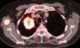

Pancreatic cancer metastasis

Metastasis is a pathogenic agent's spread from an initial or primary site to a different or secondary site within the host's body; the term is typically used when referring to metastasis by a cancerous tumor. The newly pathological sites, then, are metastases (mets). [Source: Wikipedia ]